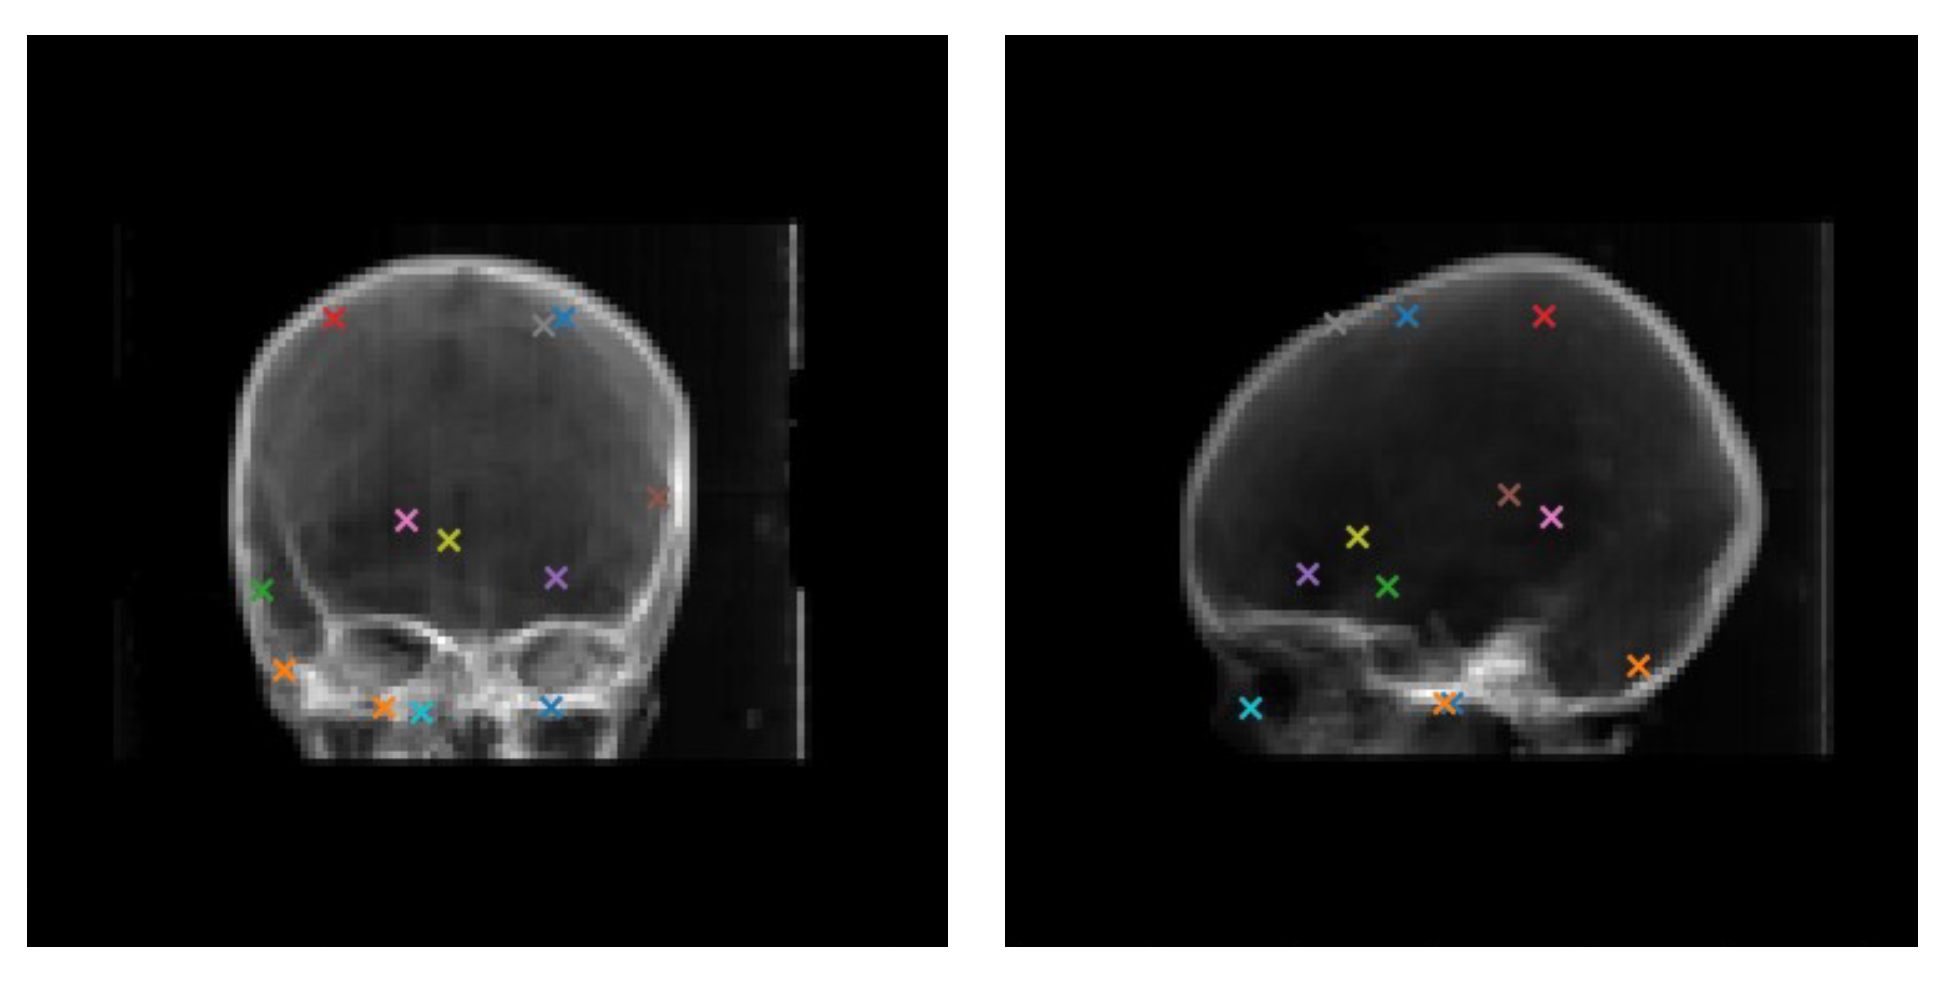

3.1. Dataset